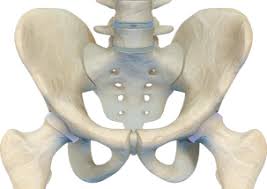

1. 고관절의 위치와 역할 ⚙️

고관절은 허벅지뼈(대퇴골)와 골반뼈(비구)가 만나는 부분으로, 걷기, 앉기, 달리기 등 대부분의 하체 움직임을 담당합니다.

공처럼 생긴 대퇴골 머리가 관절 안에 들어가 회전하면서 부드러운 움직임을 가능하게 합니다. 하지만 이 부위는 체중을 많이 받기 때문에 쉽게 손상될 수 있습니다.